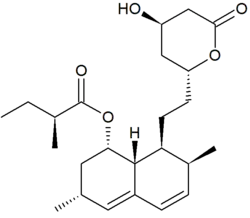

Statins are a class of lipid-lowering medications used in the treatment and prevention of cardiovascular disease, specifically those associated with LDL-C.[12] Statins have been shown to reduce incident cardiovascular events by 30-40% when used as prescribed.[13] However, statins are associated with a range of adverse effects (e.g., statin myopathies and myalgias) sometimes severe enough warrant discontinuation and/or substitution.[14][15] For individuals completely intolerant to statins who nevertheless have an indication for lipid-lowering therapy, lipoprotein apheresis—a non-surgical method of removing lipoprotein particles from the bloodstream—is an option.

Pharmacologic inhibition of proprotein convertase subtilisin/kexin type 9 (PCSK9), an enzyme crucial for maintaining lipoprotein homeostasis, can be achieved through the use of monoclonal antibodies targeting PCSK9, such as evolocumab and alirocumab. This approach offers a potential solution for individuals with statin intolerance and insufficient response to statins alone, a common scenario among patients with familial hypercholesterolemia—whereby significant reductions in circulating lipoproteins can be achieved.[13]